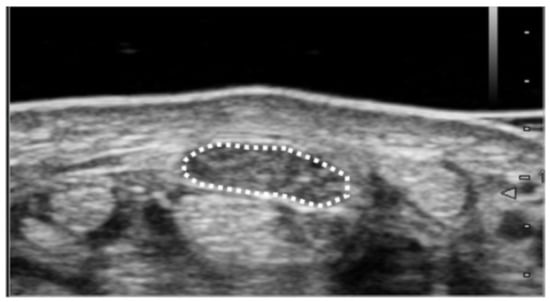

| Cross-sectional area (mm2) | 14.2 ± 4.0 | 11.3 ± 2.7 | 0.74 | 11.9 |